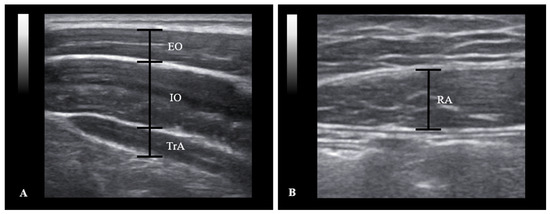

2.2. Materials